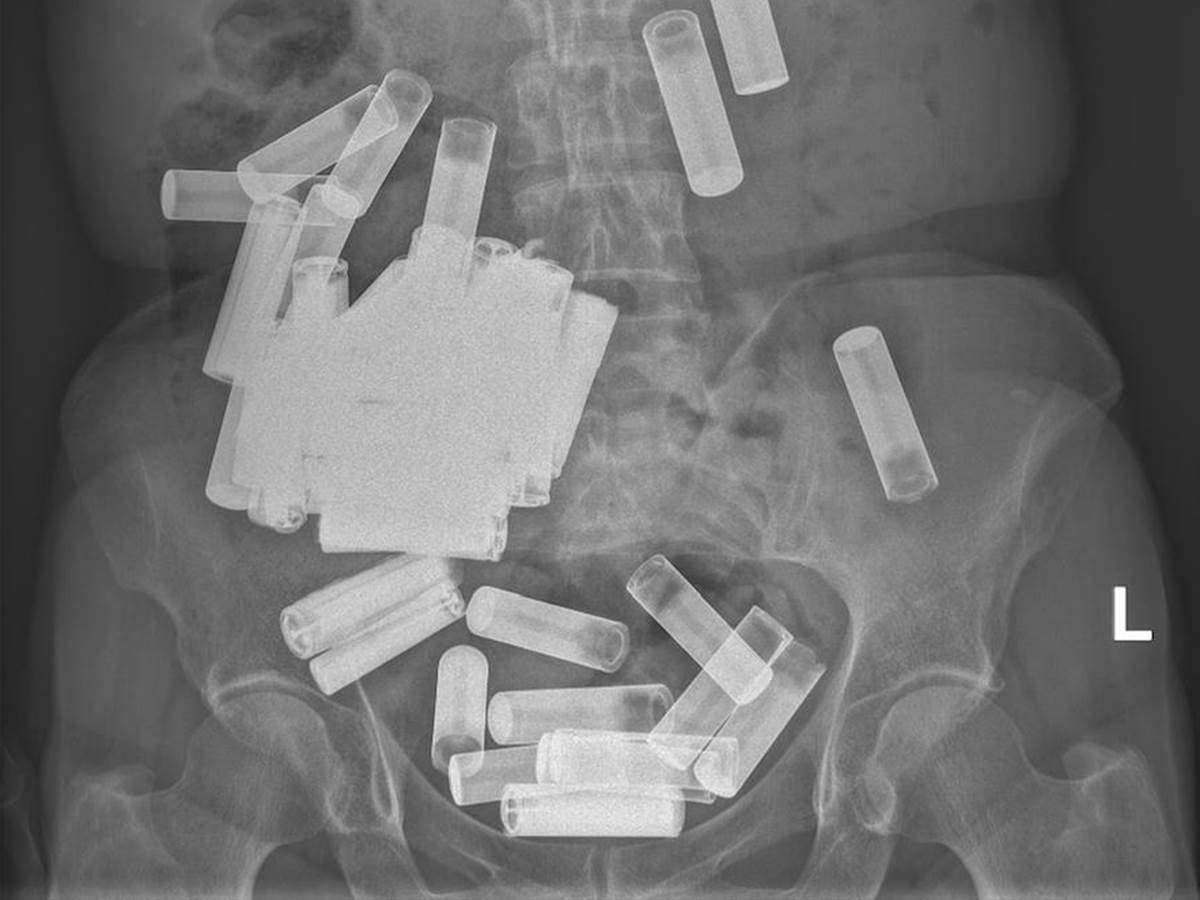

Lekari na Univerzitetu Sent Vinsent u Dablinu uklonili su preko 50 baterija iz creva i želuca jedne starije žene nakon što je rendgenski snimak otkrio da šta se krije u njenom stomaku.

Naime, u činu samopovređivanja, 66-godišnja žena je namerno progutala baterije. Srećom, kada se pojavila u bolnici Univerziteta, baterije nisu blokirale njen digestivni trakt, a rendgenski snimak takođe nije pokazao znakove strukturnog oštećenja baterija.

Doktori su prvo zauzeli konzervativan pristup ne bi li videli da li baterije mogu same da prođu kroz digestivni trakt bez ikakve intervencije. Posmatrali su je nedelju dana, tokom kojih je pacijentkinja uspela da izbaci pet AA baterija. Međutim, kako u naredne tri nedelje žena nije uspela da izbaci preostale baterije, počela je da oseća bolove u stomaku i lekari su morali da intervenišu.

Tim hirurga je izveo proceduru koja se naziva laporotomija, tokom koje je napravljen rez kako bi se pristupilo njenoj trbušnoj duplji. Otkrili su da joj se stomak usled težine baterija proširio u područje iznad pubične kosti.

Srećom po pacijentkinju, hirurzi su iz njenog stomaka uspešno izvadili preostalih 50 baterija, od kojih su neke bile i manje, odnosno AAA baterije, što znači da je žena progutala ukupno 55 baterija.

"Prema našim saznanjima, ovaj slučaj predstavlja najveći prijavljeni broj baterija progutanih u jednom trenutku", napisali su doktori u svom izveštaju za Irish Medica Journal.